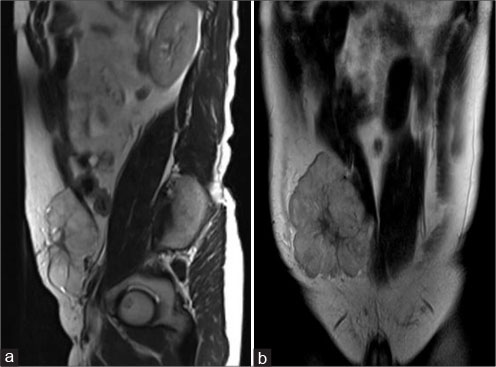

| Figure 4: Magnetic resonance imaging of the abdomen - sagittal T2 (a), coronal T2 (b) showing well-definedsolid mass with lobulated outlines in the right iliac fossa and hypogastric region in subcutaneous plane causing extrinsic compression and posterior displacement of abdominal wall muscles appearing hyperintense on T2-weighted image

A 40-year old male patient presented with swelling over the anterior abdominal wall on the right side in lower abdomen for 1 month which was rapidly increasing in size. There was a history of weight loss. The mass was painless. The ultrasonography showed a large, well-defined solid mass with lobulated outlines in anterior abdominal wall in the right paraumbilical and hypogastric region [Figure 1]. The mass was seen in the subcutaneous plane, causing extrinsic compression on adjoining right rectus abdominis and external oblique muscle. It was predominantly hypoechoic with small areas of the necrosis in its center and showed mild vascularity on color Doppler. No calcification was seen. Plain and contrast enhanced computed tomography (CT)-scan of the abdomen and pelvis was performed. A large, well defined solid mass with lobulated outline measuring approximately 96 mm × 38 mm × 98 mm in transverse, anteroposterior and craniocaudal dimension was noted in the anterior abdominal wall on the right side in right iliac region extending to hypogastric region. It was slightly hypodense with respect to muscle on the plain study with a CT value of 35–45 HU and showed a mild heterogeneous enhancement in contrast study (CT value 55–65 HU). No calcification was noted. The mass was in subcutaneous plane and was extending anteriorly up the skin. Posteriorly, it was causing mass effect on the right rectus abdominus and adjoining external oblique and internal oblique muscles which were compressed and displaced posteriorly with obliteration of intervening fat planes [Figure 2]. An enhancing vessel was noted in the right rectus abdominus extending into the mass suggestive of neovascularity. No intra-abdominal extension was noted. Rest of the abdominal wall appeared normal. No hepatic or adrenal metastases, intra-abdominal lymphadenopathy noted. On magnetic resonance imaging (MRI), the mass appeared slightly hyperintense with respect to muscle on T1-weighted image, heterogeneously hyperintense on T2-weighted image (T2WI), and hyperintense on short tau inversion recovery and showed restricted diffusion on diffusion-weighted imaging with low apparent diffusion coefficient (ADC) values (ADC = 800). It was causing mass effect on the right rectus abdominus and adjoining external oblique and internal oblique muscles [Figure 3] [4] [5] [6].